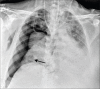

Results: 756 RT-PCR confirmed COVID-19 patients were included in our study who had initial CXR. 510 (67.46%) of our patients with positive initial RT-PCR showed abnormal baseline CXR. The abnormal findings were described as haziness akin to ground glass opacities (GGO) on CT, peripheral opacities, patchy parenchymal opacities and consolidation. Peripheral opacities and lower zone distribution were the commonest pattern of CXR abnormalities with bilateral involvement. The severity of findings on serial CXR and radiographic regression was studied along with follow-up to assess response to treatment. Forty-six patients showed features of acute lung injury (ALI). Complications and new CXR findings were reported for patients who were given ventilator support.